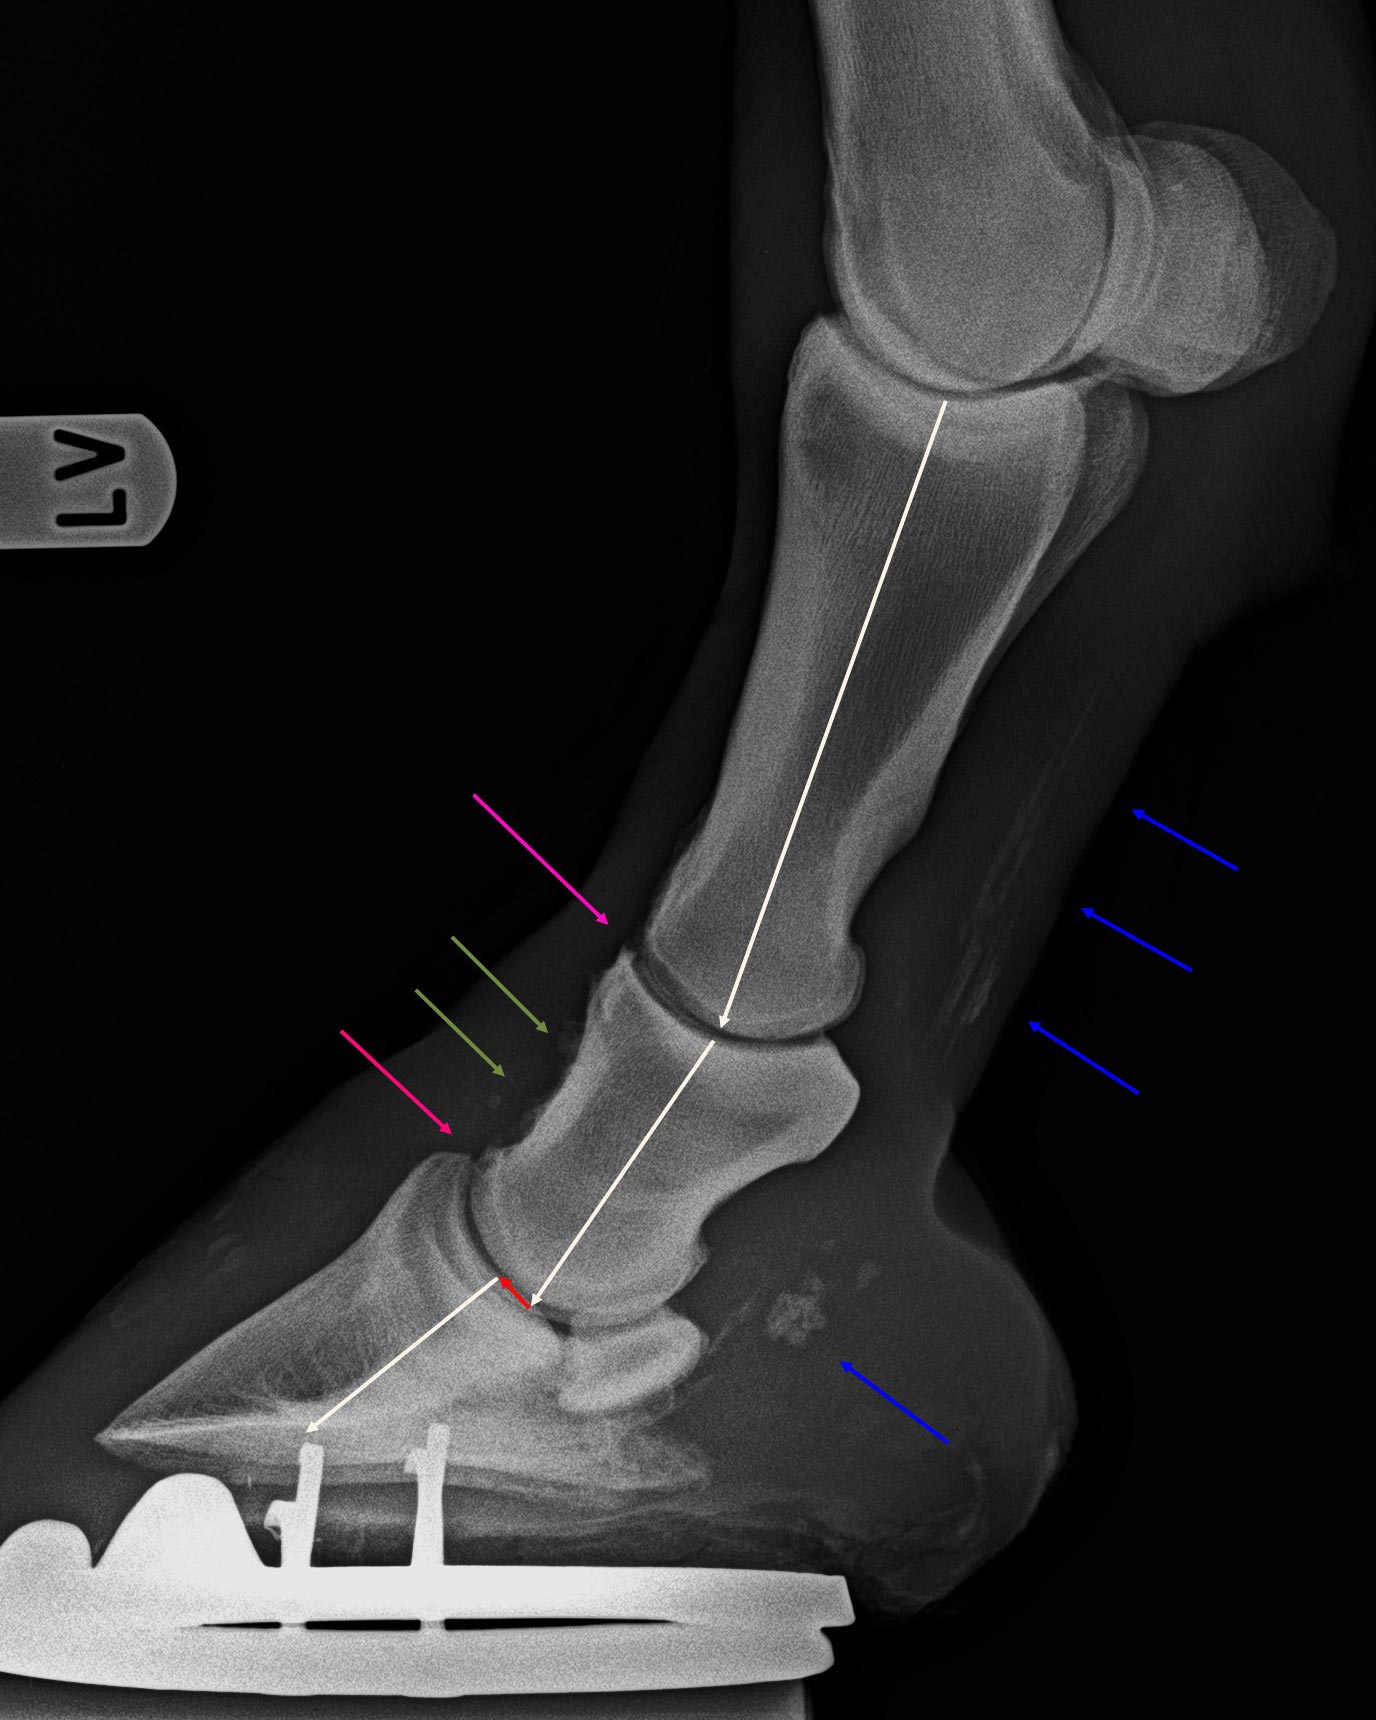

Zehe vorne links - 90°-Aufnahme

Sehnenverkalkungen (blaue Pfeile), geringgradige Kron- und Hufgelenksarthrose (violette Pfeile),

dorsale Exostosen auf dem Kronbein (grüne Pfeile) und Subluxation im Hufgelenk (roter Pfeil)